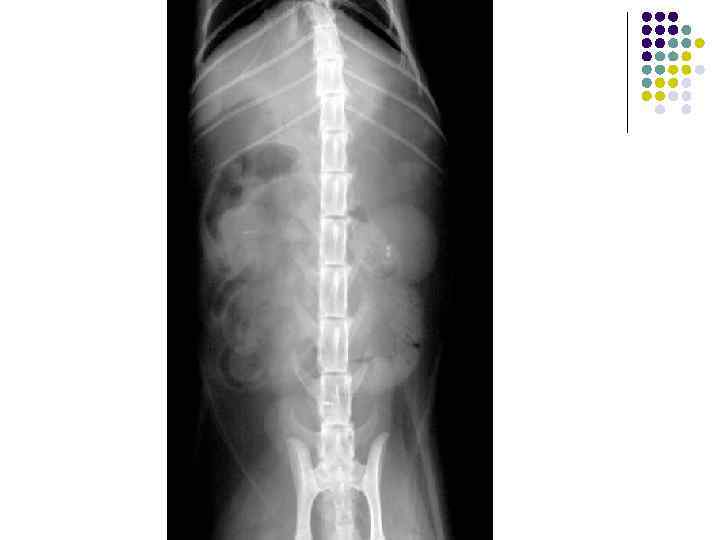

Брюшная полость собаки